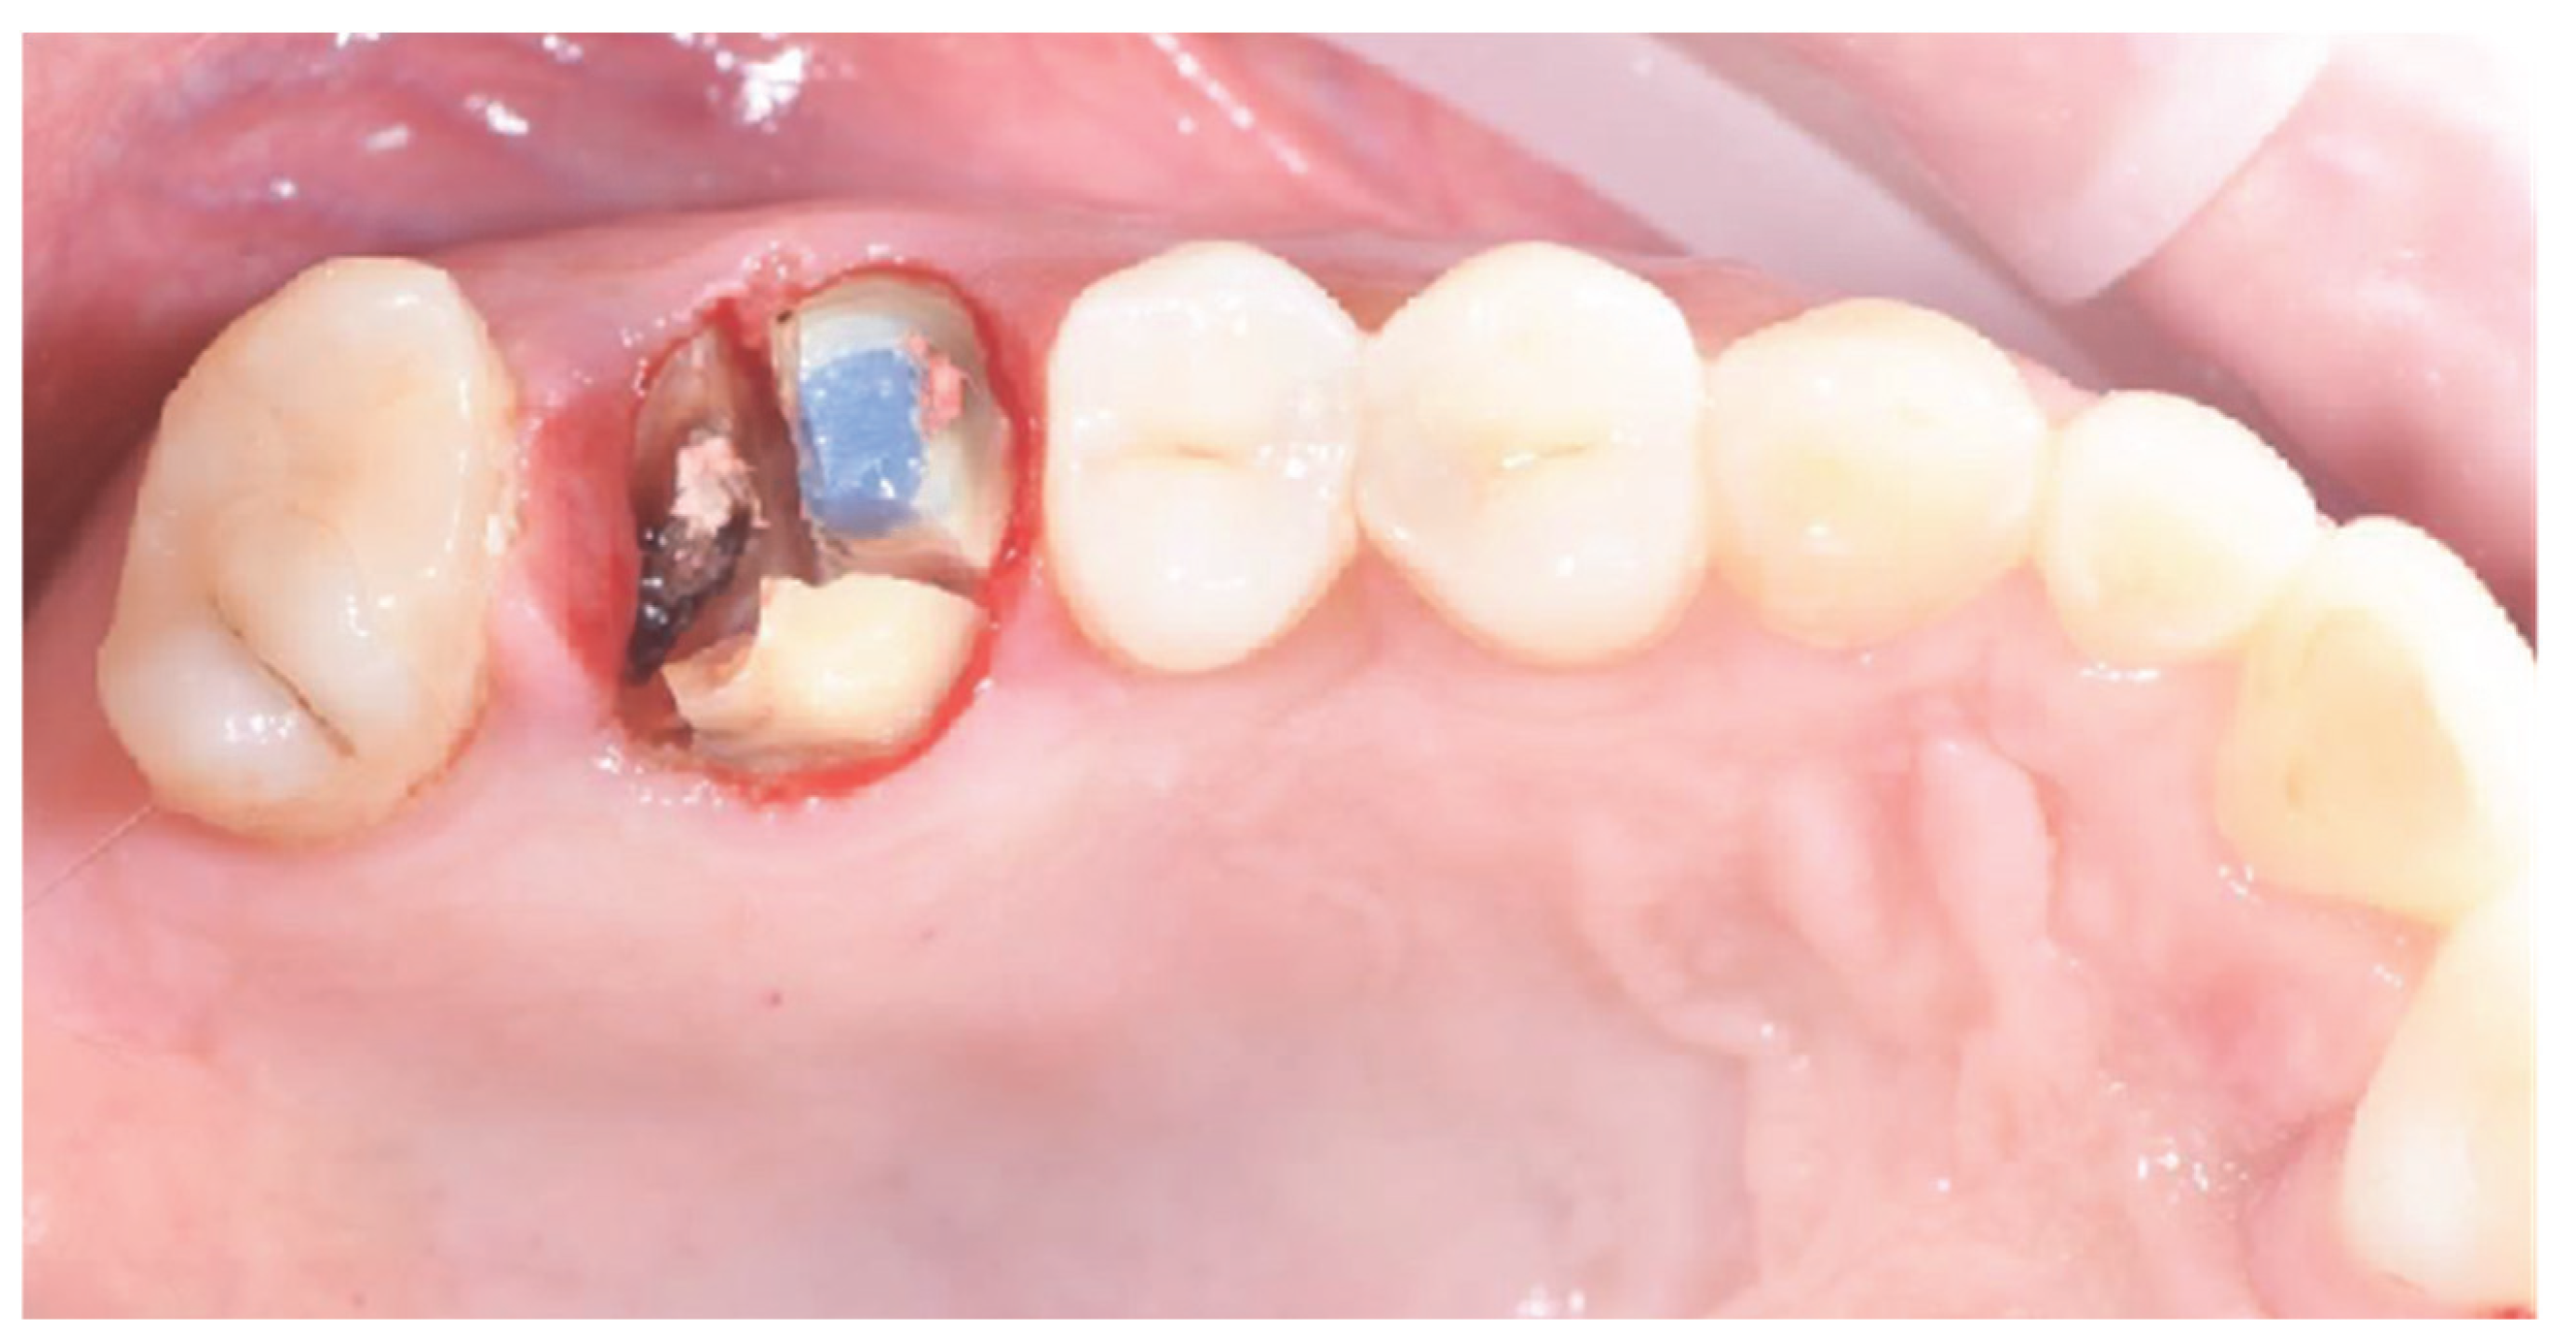

2.1. Socket Preservation Procedure